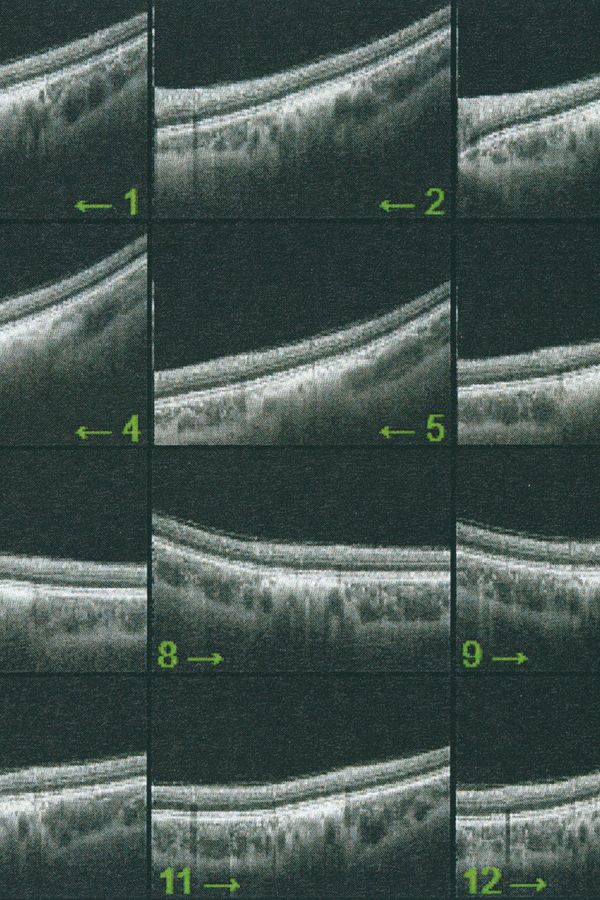

Following a terrifying experience with a too high dose of LSD when I was 16, something has changed in the way I observe visible reality. A hypertrophic screen materialized between me and the world, a scar of opacity. The fear of hallucination teaches a new language, so that every meaning remains trapped in a net and only the signifier filters through its meshes. No shadow, only empty light. Anguish arrests every retinal projection on that screen. Every perception is immobilized to be inspected for a hallucinatory return, it is reified, detached from its real referent, reduced to representation, incapable of referring to something outside of it. And behind (or in front) of it, the eyes have stolen consistency from reality. The body only appears occasionally, at the edges of the mind, when we engage in apperception. And yet I feel the tinkling of a gear that draws my attention inside my eye. I reflect on myself, I look back and from the inside. Once vision is situated in the empirical immediacy of the body, it belongs to time, to flow, to the end.

Collirio (Eye wash) is the attempt to demonstrate the non-absoluteness of visual experience, its nature as a situated, and yet, ambiguous act. It is the path that has allowed me to understand how my fears do not have roots in an unknowable place. The eye is not an unfathomable globe.